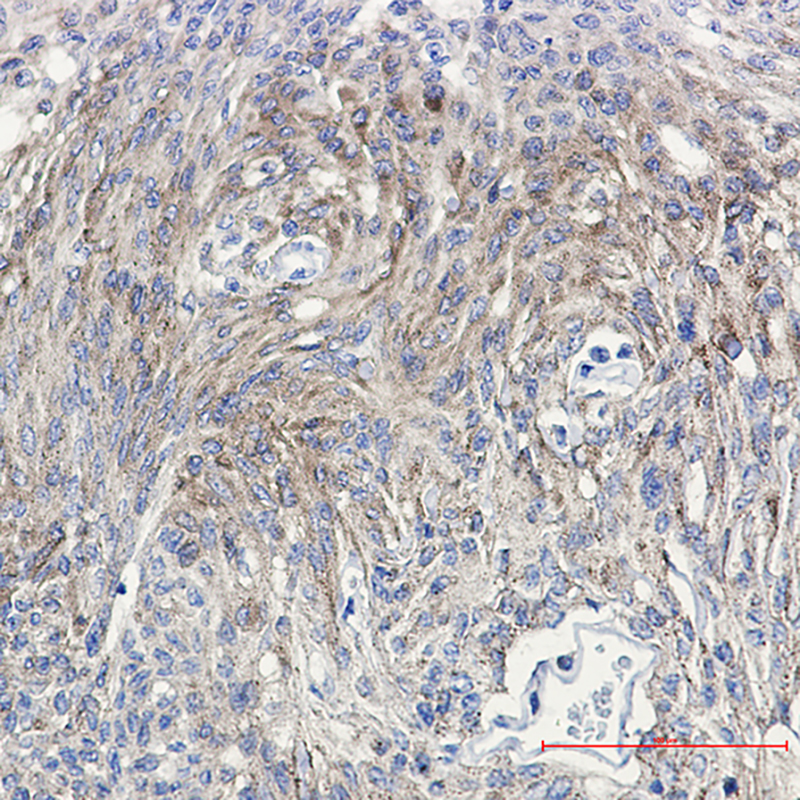

Immunohistochemistry analysis of paraffin-embedded Human Brain using PKC (Phospho-Thr514) antibody. High-pressure and temperature Sodium Citrate pH 6.0 was used for antigen retrieval.